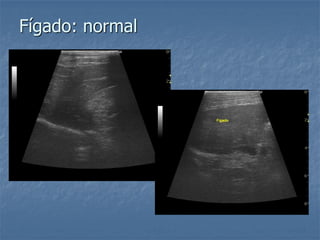

Fígado: normal

Fígado normal tórax profundo

Gás em cavidade gástrica

diafragma